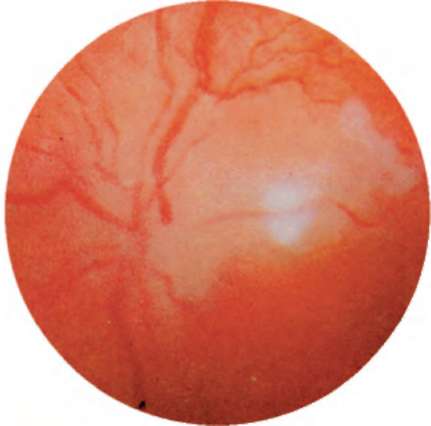

Рис. 12.6. Первичная атрофия диска зрительного нерва